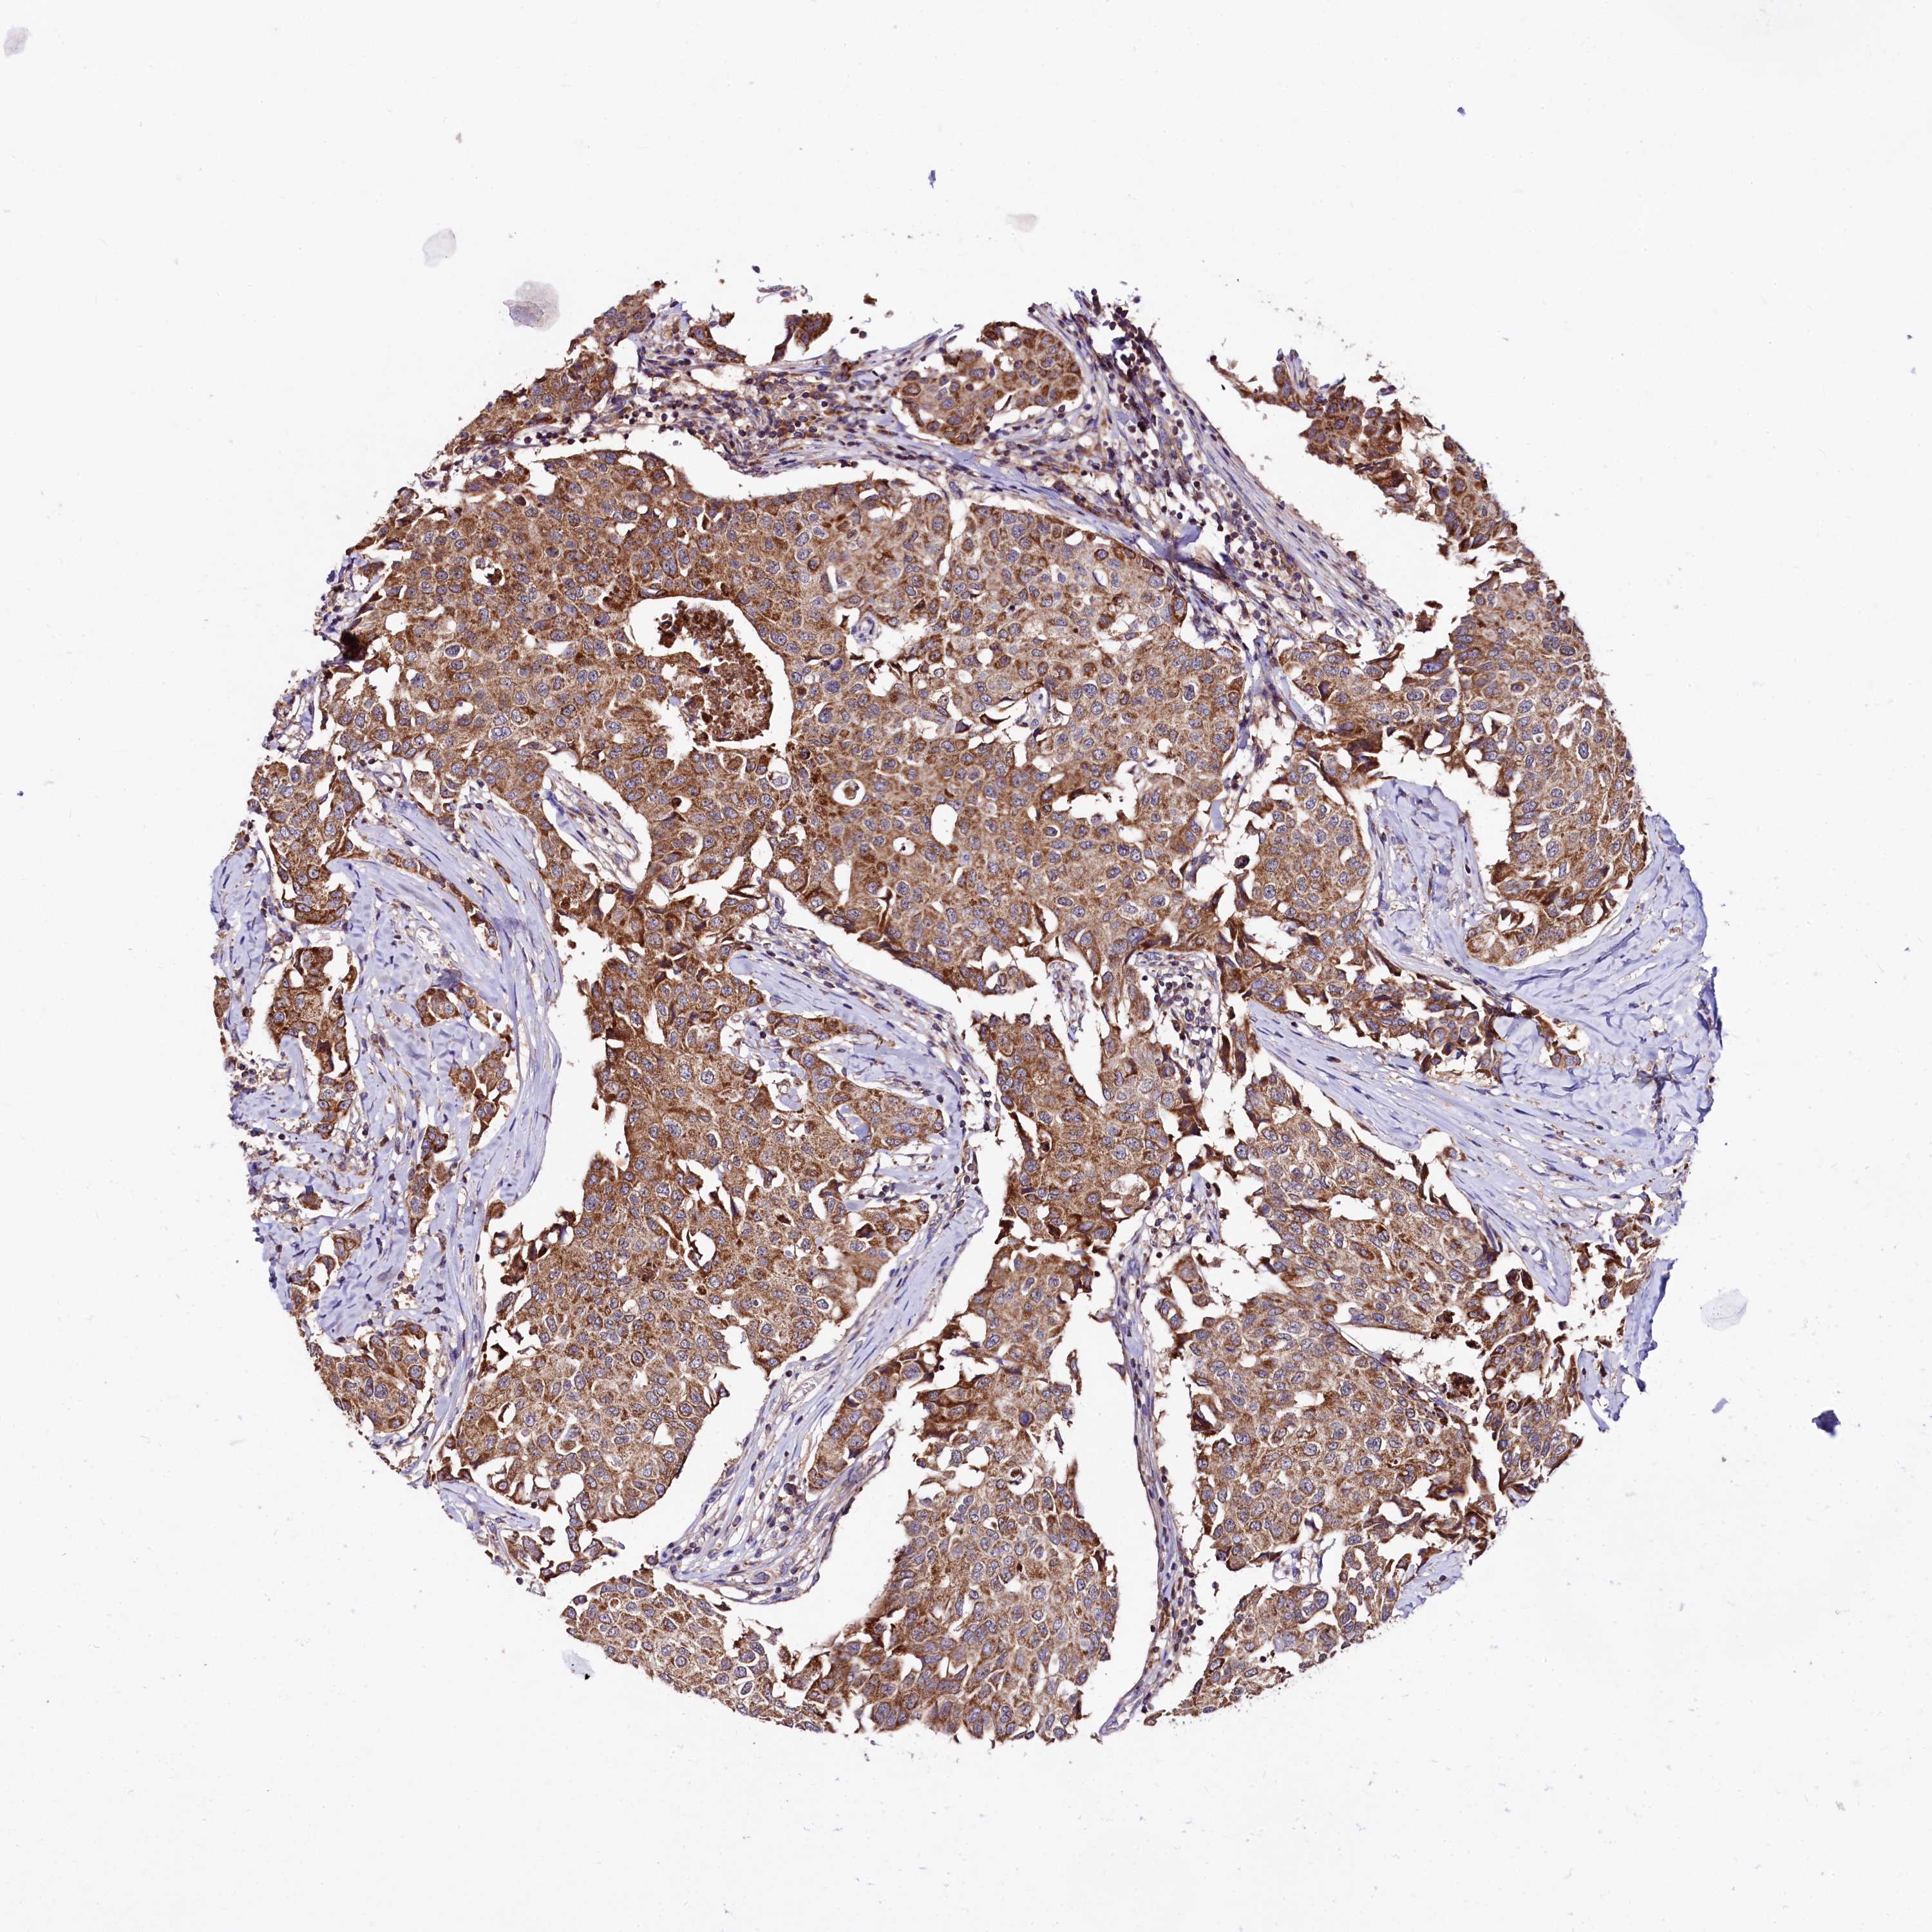

CANCER BREAST CANCER Show tissue menu

BRCA TCGA BRCA VALIDATION PROTEIN EXPRESSION